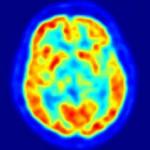

Métodos: Se aplica Tomografía por emisión de positrones Tau (PET) con 18F T807 (AV 1451), PET β amiloide usando 11C compuesto Pittsburgh B (PIB) en individuos clínicamente sanos de edad avanzada y pacientes sintomáticos con deterioro cognitivo leve o demencia Alzheimer leve.

Resultados: Se encuentran bandas corticales 18F T807 anormalmente altas en pacientes con deterioro cognitivo leve y demencia EA en comparación con controles clínicamente normales. En consonancia con literatura neuropatologica, la presencia de aumento de bandas 18F T807 neocorticales, especialmente en el giro temporal inferior se asoció con deterioro clínico. La asociación de deterioro cognitivo fue más fuerte con 18F T807 temporal inferior, que con media 11C cortical PIB. Regional 18F T807 se correlacionó con media de 11C cortical PiB en ambos grupos de pacientes deteriorados y controles.

Interpretación: Estos hallazgos sugieren que PET 18F T807 podría tener valor como un biomarcador que refleja tanto la progresión de taupatía EA y la aparición de deterioro clínico.